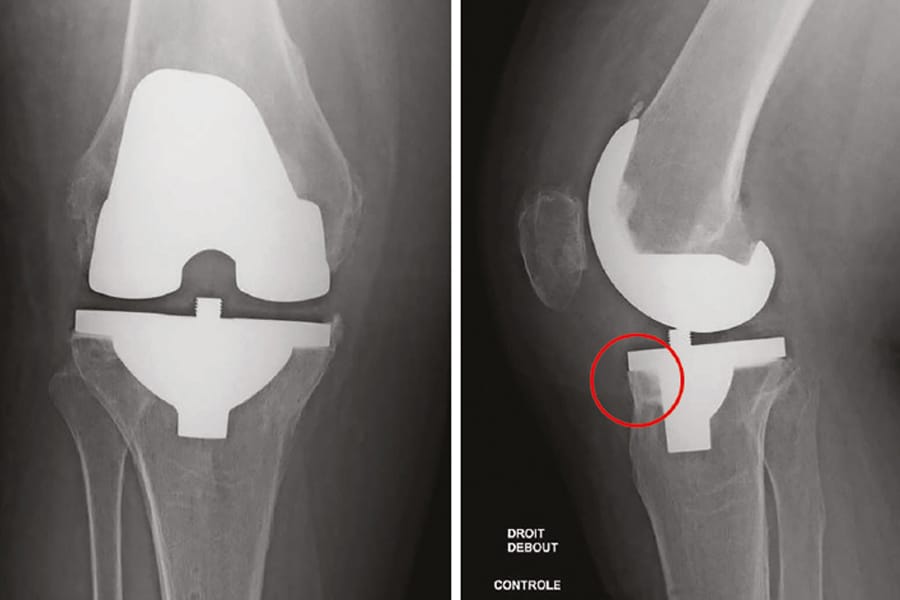

The clinical articles in this issue span infection prevention, surgical access, and ligament pathology. The prophylactic role of local antibiotics in PMMA bone cement is critically examined, followed by an evaluation of the lateral subvastus approach for Total Knee Arthroplasty and its impact on postoperative recovery. Two further contributions address ACL pathology: the management of ACL intra-substance tears in growing children and teenagers, and the incidence and risk factors for arthrogenic muscle inhibition after ACL reconstruction.